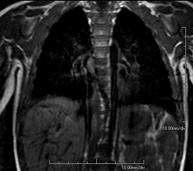

- Thorax

- Mediastinal MRI

This non-invasive diagnostic procedure uses an electromagnetic field and radio waves (from a transmitter and receiver) to acquire high-definition anatomical images of the mediastinum. It is a radiation-free procedure. The mediastinum is the central part of the rib cage that includes the thymus, the great vessels (thoracic aorta, inferior and superior vena cava, etc.), the heart, the trachea and main bronchi, mediastinal and hilar lymph nodes, the oesophagus, etc. It is especially indicated in mediastinal lesions to differentiate between cystic and solid lesions, in the differential diagnosis of anterior mediastinal lesions, etc. Sometimes paramagnetic contrast (gadolinium) must be used to complete the study.

- Chest MRI

This non-invasive diagnostic procedure uses an electromagnetic field and radio waves (from a transmitter and receiver) to acquire high-definition anatomical images of the chest. It is a radiation-free procedure. It is indicated for lung lesions in which infiltration of the mediastinum or thoracic wall must be ruled out, to differentiate between solid and cystic chest lesions, etc. Sometimes paramagnetic contrast (gadolinium) must be used to complete the study.